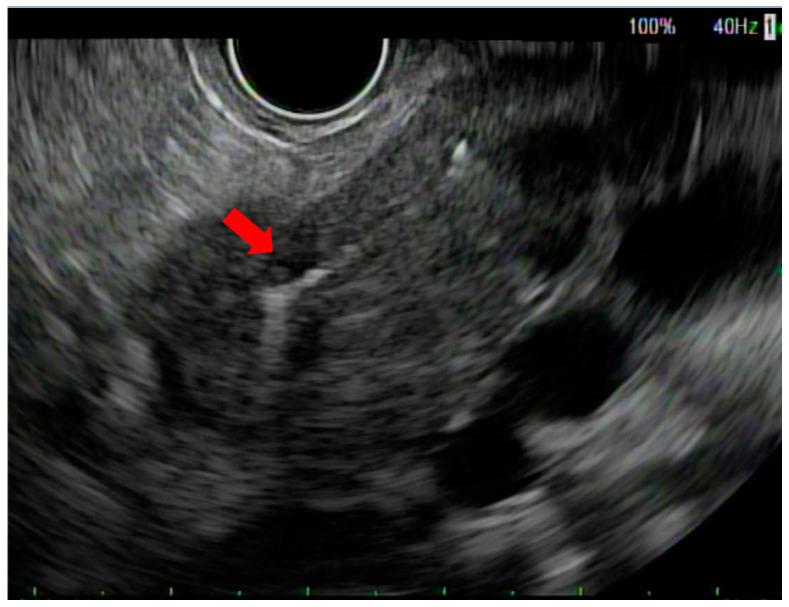

Accurate delivery of stereotactic body radiotherapy (SBRT) to pancreatic tumors relies on successful EUS-guided placement of fiducial markers. The aim of this study is to report the technical feasibility and safety of EUS-guided fiducial placement and to evaluate the characteristics and technical benefit of SBRT in a cohort of patients with pancreatic cancer (PC). A retrospective chart review was performed for all ( = 82) PC patients referred for EUS-guided fiducial placement by a single endosonographer at a tertiary cancer center. Data regarding EUS-related technical details, SBRT characteristics, adverse events, and continuous visibility of fiducials were recorded and analyzed. Most patients included in the study had either locally advanced disease (32 patients, 39%) or borderline resectable disease (29 patients, 35%). Eighty-two PC patients underwent the placement of 230 fiducial markers under EUS guidance. The technical success rate of the fiducial placement was 98%. No immediate EUS-related adverse events were reported. The average time to the simulation CT after fiducial placement was 3.1 days. Of the 216 fiducial markers used for the SBRT delivery, 202 fiducial markers were visible on both the simulation CT and the cone beam CT scan. A median dose of 40cGY was given to all the patients in five fractions. Of these, 41% of the patients reported no SBRT-related toxicities during the follow-up. Fatigue and nausea were the most reported SBRT-related toxicities, which were seen in 35% of the patients post-SBRT. Our results demonstrate that EUS-guided fiducial placement is safe and effective in target volume delineation, facilitating SBRT delivery in PC patients. Further clinical trials are needed to determine the SBRT-related survival benefits in patients with pancreatic cancer.